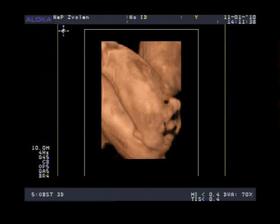

- 11.1.10 sme boli na 3D a pan doktor nam povedal ze to vyzera na DIEVČATKO 🙂